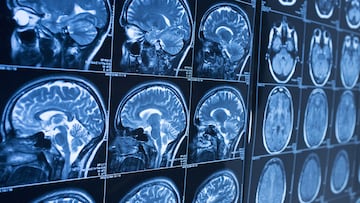

Un equipo de investigadores de la University of Cambridge dio a conocer un hallazgo revolucionario en neurociencia, ya que la adolescencia cerebral se extendería hasta aproximadamente los 32 años. El trabajo, publicado en la revista Nature Communications y, basado en resonancias magnéticas de unas 3,800 personas de entre 0 y 90 años, identifica cuatro “puntos de inflexión” clave en el cerebro: a los 9, 32, 66 y 83 años.

Durante la infancia (0–9 años) el cerebro construye redes neuronales intensas; proliferan las conexiones y muchas sinapsis, luego se “deshace” lo que no se usa. A partir de los 9 años comienza lo que los científicos ahora llaman adolescencia cerebral, una etapa de refinamiento, donde la materia blanca del cerebro se incrementa, las conexiones se afinan y la eficiencia cognitiva crece progresivamente.

Según los autores, ese desarrollo continúa hasta cerca de los 32 años, cuando el cerebro alcanza su máxima eficiencia estructural. “El cerebro se reconfigura durante toda la vida. Fortalece y debilita conexiones, y no sigue un patrón estable”, explicó la investigadora Alexa Mousley, una de las responsables del estudio.